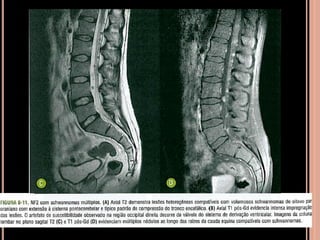

Escoliose:

 Ocorre em cerca de 10% dos pacientes

 Distróficas: remodelamento das vértebras,

alargamento do canal vertebral e dos forames

espinhosos; início precoce e rapidamente

progressiva;

 ou não distróficas = escoliose idiopática

NF1

 Costelas em fita;

 Múltiplas pseudoartroses: comprometimento da

tíbia é o mais comum;

 Hipoplasia dos elementos vertebrais posteriores;

 Remodelamento dos corpos vertebrais (10%);